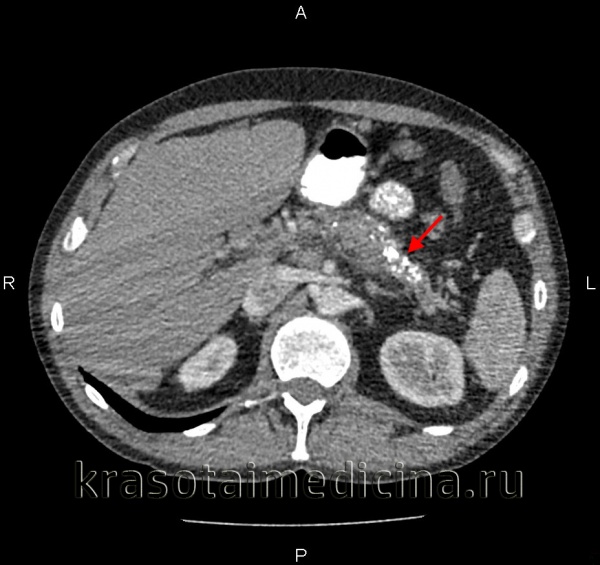

![КТ органов брюшной полости. Множественные кальцинаты в области хвоста и тела поджелудочной железы (последствия множественных острых эпизодов панкреатита)]()

КТ органов брюшной полости. Множественные кальцинаты в области хвоста и тела поджелудочной железы (последствия множественных острых эпизодов панкреатита)